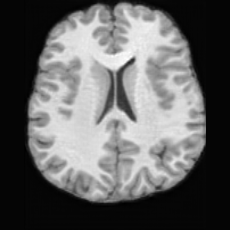

PathologicalHealthyDifferencew/o ACGw/ ACG(a)Refer to captionRefer to captionRefer to captionRefer to captionRefer to captionHealthyPathologicalDifferencew/o ACGw/ ACG(b)Refer to captionRefer to captionRefer to captionRefer to captionRefer to caption

Figure 6: Ablation study of Anatomy Consistency Guidance (ACG): (a) pathology-to-healthy; (b) healthy-to-pathology. Without ACG, edits cause anatomical inconsistencies outside lesions (arrows), whereas ACG keeps modifications lesion-focused.

Anomaly Consistency Guidance. Fig. 6 demonstrates the effectiveness of the proposed Anatomy Consistency Guidance (ACG) on bidirectional editing. Without ACG, the generated brains exhibit noticeable and unrealistic anatomical deformations in non-lesion regions (arrow-indicated), leading to structural inconsistencies between the edited and original brains, as shown in the corresponding difference maps. After incorporating ACG, the model effectively constrains editable modifications within pathological regions, while preserving the remaining anatomy. Tab. 4 further reports their quantitative performances: removing ACG leads to a substantial degradation in all L1, PSNR, and SSIM scores, reaffirming the critical role of ACG in achieving more accurate and structurally consistent reconstructions.